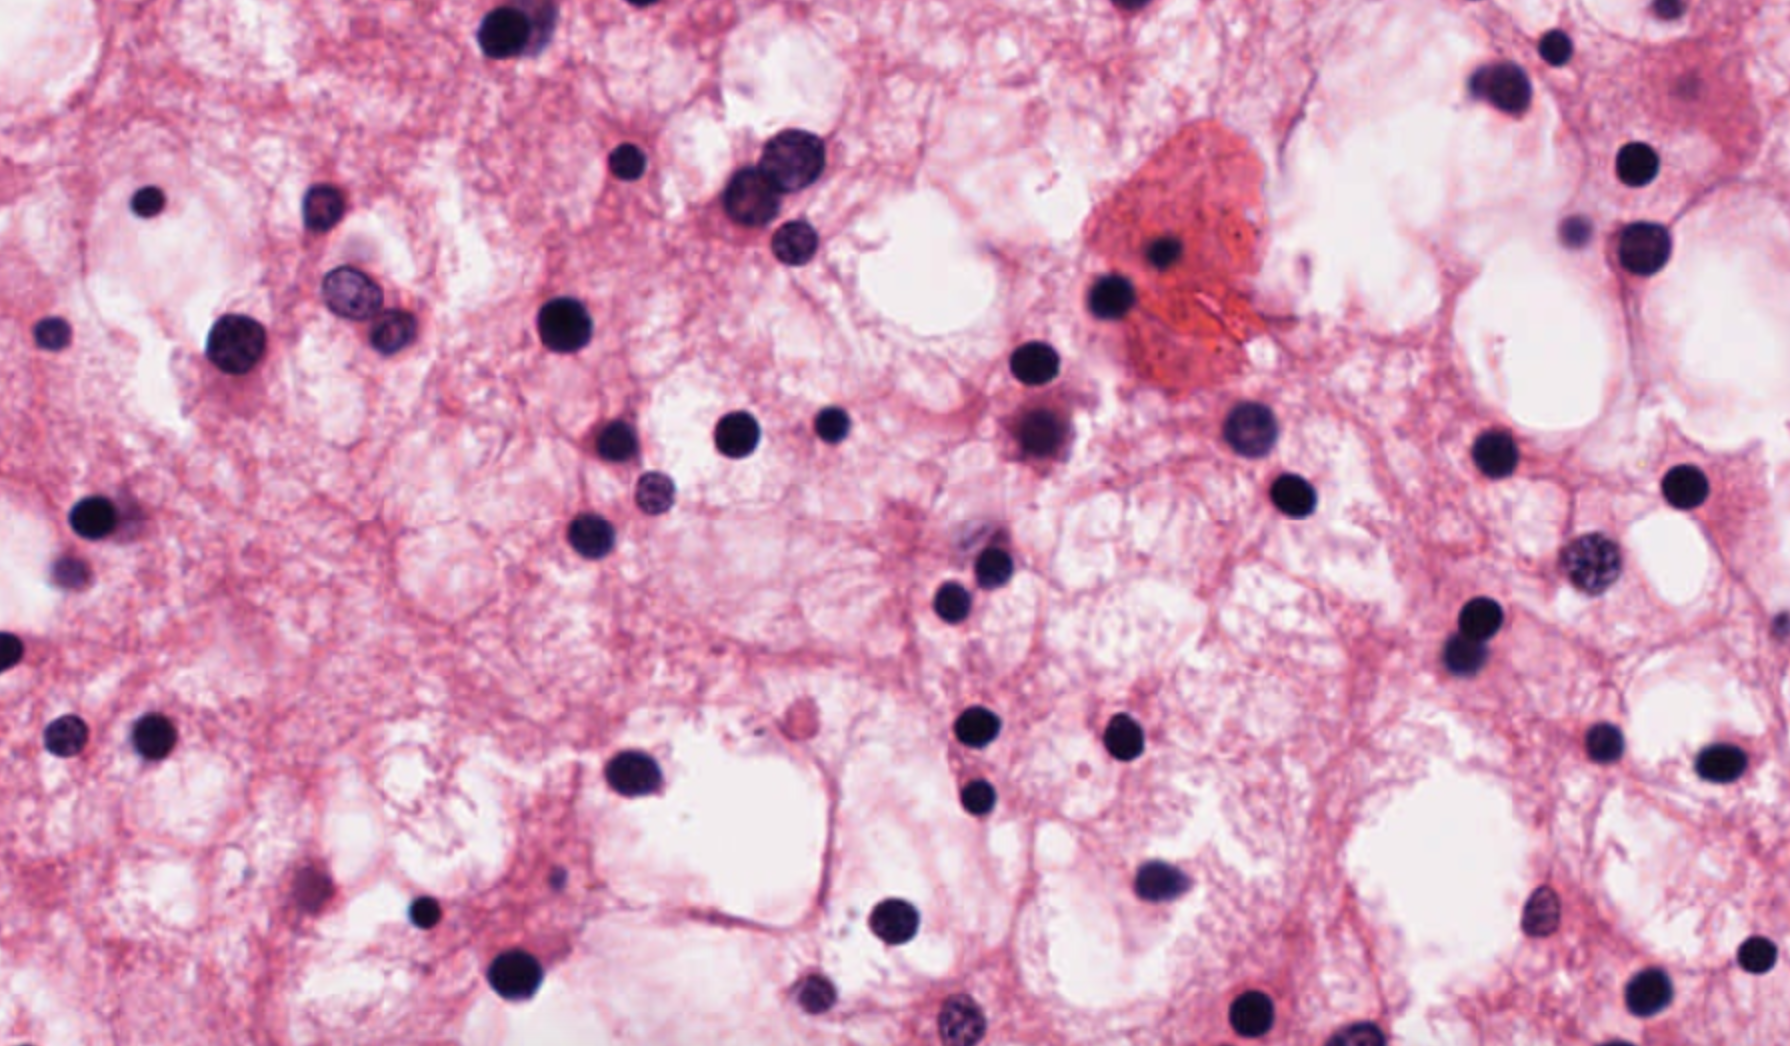

H & E (hematoxylin and eosin) are stains used to color parts of cells in a histological image, often for medical diagnosis. Hematoxylin is a compound that stains cell nuclei a purple-blue color. Eosin is a compound that stains extracellular matrix and cytoplasm pink. However, the exact color of purple-blue or pink can vary from image to image, and this can make comparison of images difficult. This routine addresses the issue by re-coloring one image (the first image supplied to the routine) using the color scheme of a reference image (the second image supplied to the routine). The technique requires that the images have at least 3 colors, such as red, green, and blue (RGB).

The following example transforms this input image

using the color scheme of this reference image

to produce this output image